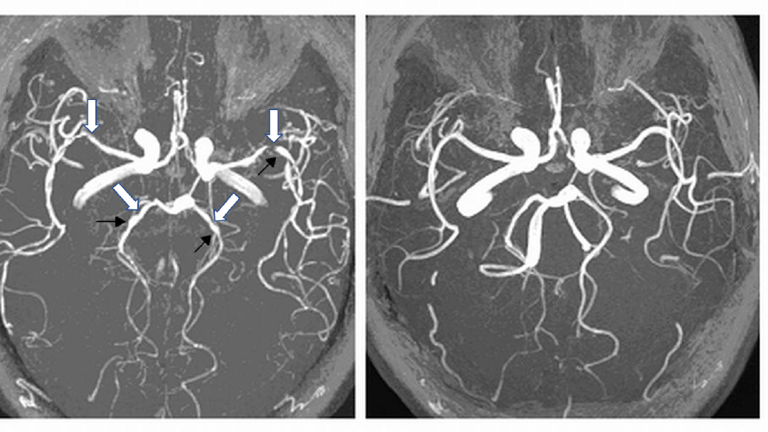

文章插圖

左一為正常大腦,由左至右為腦出血、腦中風及腦水腫的樣子。(圖/陳世彬提供)